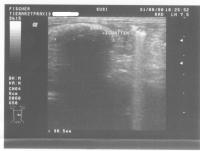

Ultraschallbilder:

Ultraschall1 Ultraschall2